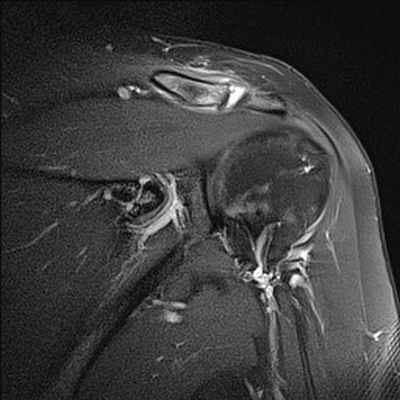

МРТ признаки повреждения акромиально-ключичного сочленения на уровне плечевого сустава

МРТ плечевого сустава